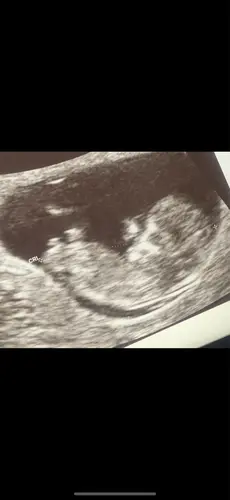

Ha! Ik ben 10+4 weken, is hier al iets op te zien? Ik snap niet zo goed hoe ik hiernaar moeten kijken. Wat denken jullie? 🥰